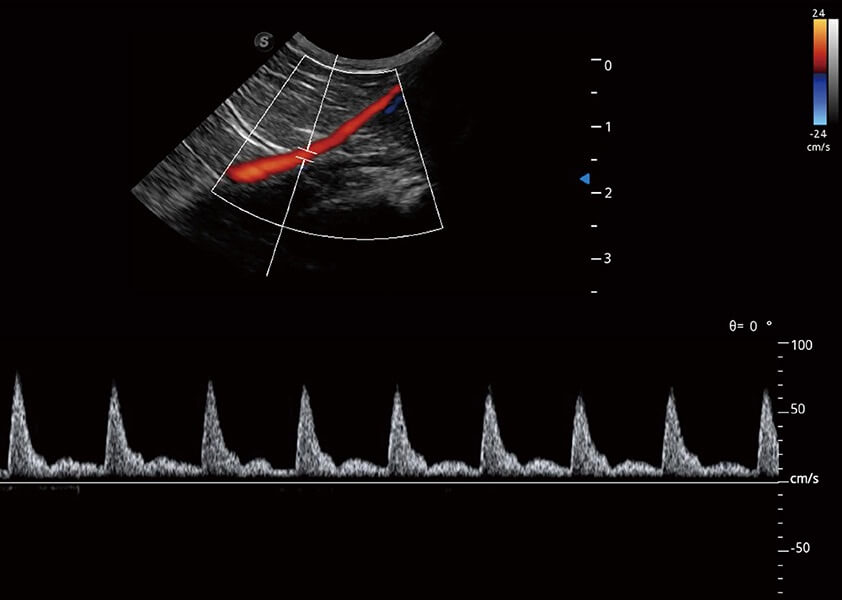

ProPet 60 作为一款高端台式动物超声设备,为动物医生的日常诊断提供了一系列贴合动物临床需求、解决临床实际问题的高级成像功能。凭借全系列高清探头,满足医生对腹部、心脏、生殖、浅表、肌骨等成像的所有需求,切实帮助您提升检查效率,提高诊断信心。

动物是人类最亲密的朋友和最值得信赖的伙伴。银河优越会也一直致力于探索动物专用的超声影像解决方案。 全新推出的ProPet系列,是银河优越会在动物超声影像智能化、专业化、精准化的一次跨越式革新。动物不能用言语来表述自己的不适,通过超声影像,ProPet系列搭建了动物医生与不同物种沟通的“桥梁”,为动物医生注入了“治愈之力”。